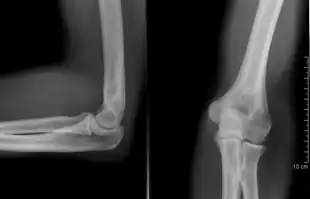

Right: AP X ray of a dislocated right elbow

The types of disease most commonly seen at the elbow are due to injury.

There are three bones at the elbow joint, and any combination of these bones may be involved in a fracture of the elbow. Patients who are able to fully extend their arm at the elbow are unlikely to have a fracture (98% certainty) and an X-ray is not required as long as an olecranon fracture is ruled out.[27] Acute fractures may not be easily visible on X-ray.[28]

Dislocation

Elbow dislocations constitute 10% to 25% of all injuries to the elbow. The elbow is one of the most commonly dislocated joints in the body, with an average annual incidence of acute dislocation of 6 per 100,000 persons.[30] Among injuries to the upper extremity, dislocation of the elbow is second only to a dislocated shoulder. A full dislocation of the elbow will require expert medical attention to re-align, and recovery can take approximately 8–14 weeks.